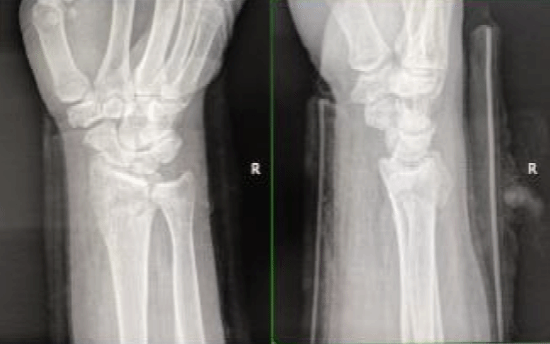

骨折手法整复、小夹板固定、固定后外观及复查X片